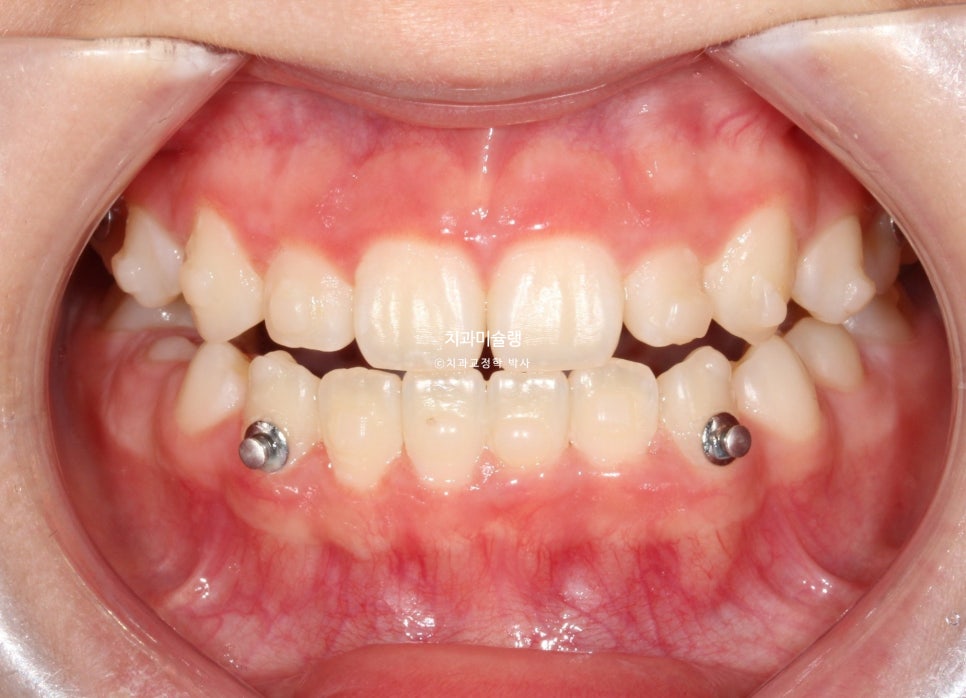

11개 장치를 다 낀 후 모습입니다.

아래 앞니가 계획만큼 뒤로 들어가지 못해서 앞니가 여전히 먼저 닿습니다.

3급 교합관계가 여전히 남아있습니다.

3급 교합관계 개선을 위해 두번째 재제작에 들어갑니다.

마지막 세트 장치 갯수는 17개이며 마찬가지로 3급 고무줄을 내내 열심히 끼도록 당부했습니다.